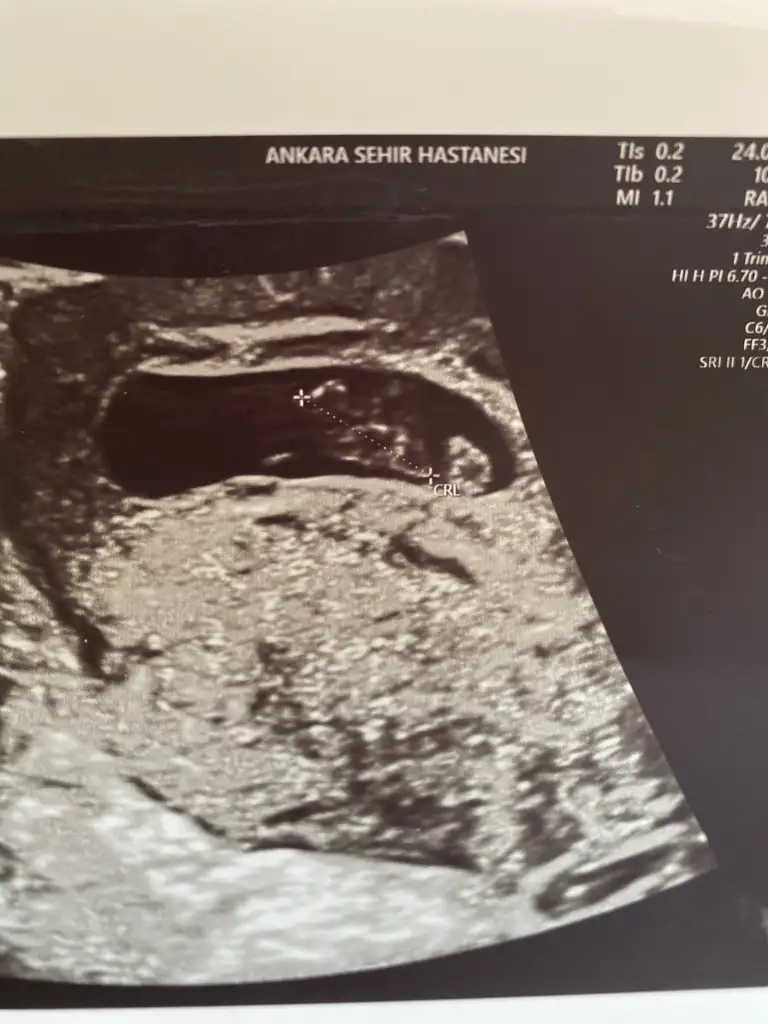

Benımkıne de yorum yapabılır mısınız lütfen

Eklentiler

• FBE62053-29CE-4EAD-A054-BFA91BC1A4C1.webp

15,2 KB · Görüntüleme: 68

• F1174268-F22C-41B2-98C8-108577C0F657.webp

11,2 KB · Görüntüleme: 65